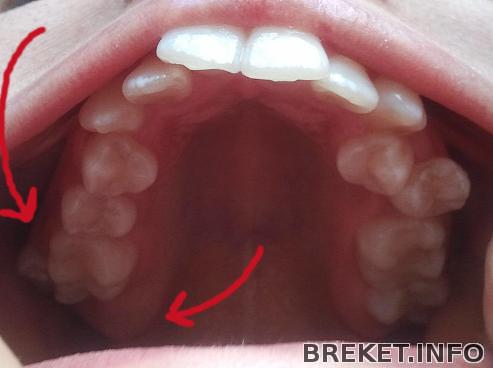

8-ки еще не прорезались, орт про них ничего не говорил, удалять будем 5-ки. Я боюсь, что в процессе лечения мне скажут удалять зубы мудрости =( а это, по-моему, самое ужасное, особенно непрорезавшиеся...

А еще меня смущает 8-ка на ВЧ справа, которая стоит бок о бок с дистопированной(!) 7-ой (на снимке все это дело слева и не совсем понятно, потому что друг на друга они залезают)...что-то я за это волнуюсь